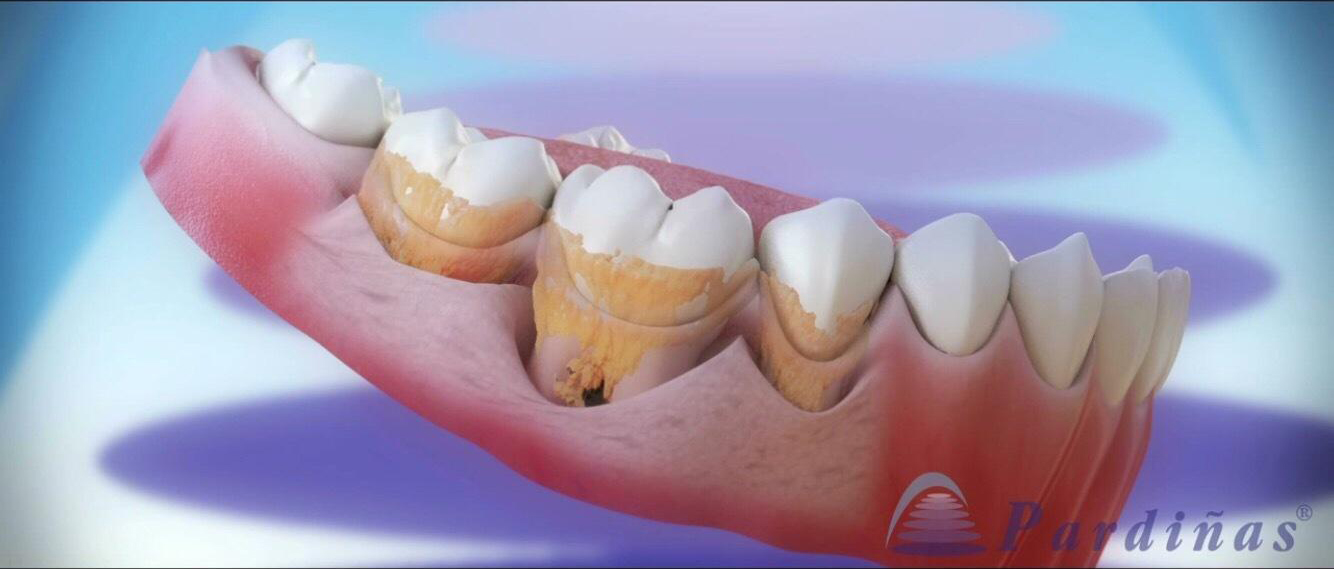

牙周病的五步治疗法